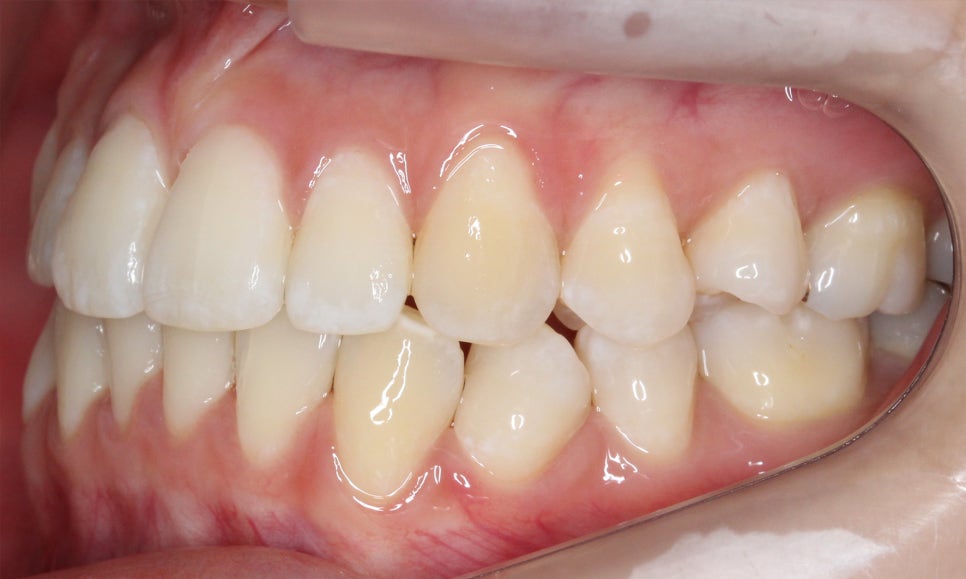

신논현치과 환자분의 클리피씨교정 후

치아의 정면 모습입니다.

교정 전 모습과 비교해보면 상하악의

중심이 바르게 잡힌 모습으로

거꾸로 교합되던 상악 측절치도

바르게 물리고 있는 것을 확인할 수 있습니다.

하악의 경우 전치부의 crowding이

사라지고 치아가 가지런하게 배열되면서

치아 사이에 블랙트라이앵글이 발생한 모습인데요,

이는 추후 레진을 올려 커버하거나 혹은

무삭제 라미네이트 '세라필름'등을 적용하여

심미성을 보완할 수 있습니다.

overbite 사진에서도 상하악이 벌어진 부분 없이

바르게 교합되고 있는 모습으로

자가결찰브라켓을 적용하였기 때문에

단기간에 교정을 마무리할 수 있었습니다.

신논현치과 환자분의 교정 후 overjet 사진입니다.

교정 전에도 전치부의 돌출감은 그다지

심하지는 않았지만 교정 후 조금 더

가지런해지고 반대교합 증상을 보이던

측절치가 올바르게 교합되면서

전치부의 심미성이 보완된 모습입니다.

좌우의 교합 평면을 보면 협측의 치아 배열이

교정 전보다 가지런해진 것을 확인할 수 있는데요,

비발치로 교정을 진행하였기 때문에

전체적인 악궁의 길이는 짧아지지 않고

삐뚤어진 치아들만 바르게 배열된 모습입니다.

하악 또한 상악과 같이 전치부에서

발견되던 crowding이 사라졌고

치열이 가지런하게 바뀐 모습을 확인할 수 있는데요,